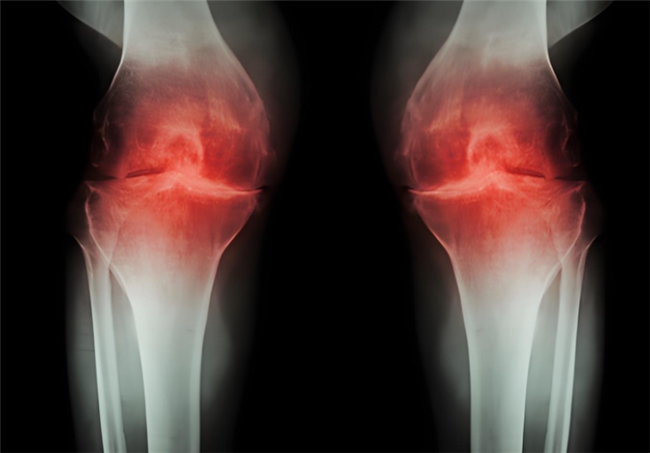

臨近年底,多地強(qiáng)降溫來襲,“老寒腿”又如期成了不少人的困擾。其實(shí),“老寒腿”并非單純的畏寒,而是骨關(guān)節(jié)炎的通俗叫法。寒冷只會誘發(fā)和加重關(guān)節(jié)疼痛、僵硬等不適,真正的患病根源是關(guān)節(jié)軟骨的磨損與退化。而氨基葡萄糖類藥物,就是直擊骨關(guān)節(jié)炎患病根源的臨床常用干預(yù)方案。不過,它還分鹽酸和硫酸氨基葡萄糖兩種,鹽酸和硫酸氨基葡萄糖的作用與功效差異在哪?該如何選對藥物、精準(zhǔn)護(hù)關(guān)節(jié)?

鹽酸和硫酸氨基葡萄糖膠囊都是氨基葡萄糖類藥物,能為關(guān)節(jié)軟骨提供合成原料,在促進(jìn)軟骨基質(zhì)的修復(fù)與再生的基礎(chǔ)上,補(bǔ)充關(guān)節(jié)滑液以減少摩擦,同時(shí)通過抑制關(guān)節(jié)腔內(nèi)的炎癥因子,從多個(gè)方面幫助延緩骨關(guān)節(jié)炎的進(jìn)展[1],但它們在臨床療效上卻存在一定差異。

根據(jù)國際醫(yī)學(xué)四大期刊之一《美國醫(yī)學(xué)會雜志》上發(fā)布的一項(xiàng)研究表明,硫酸氨基葡萄糖在緩解膝骨關(guān)節(jié)炎疼痛、改善關(guān)節(jié)活動(dòng)功能方面,效果優(yōu)于鹽酸氨糖等33種骨關(guān)節(jié)炎常用藥[2]。還有相關(guān)研究顯示,硫酸氨基葡萄糖不僅能延緩關(guān)節(jié)間隙變窄,還能從根源改善關(guān)節(jié)結(jié)構(gòu)、減緩磨損。而鹽酸氨基葡萄糖在這一關(guān)鍵指標(biāo)上的效果尚未明確。因此,在關(guān)節(jié)保護(hù)的“確切性”上,硫酸氨基葡萄糖顯然更具優(yōu)勢。